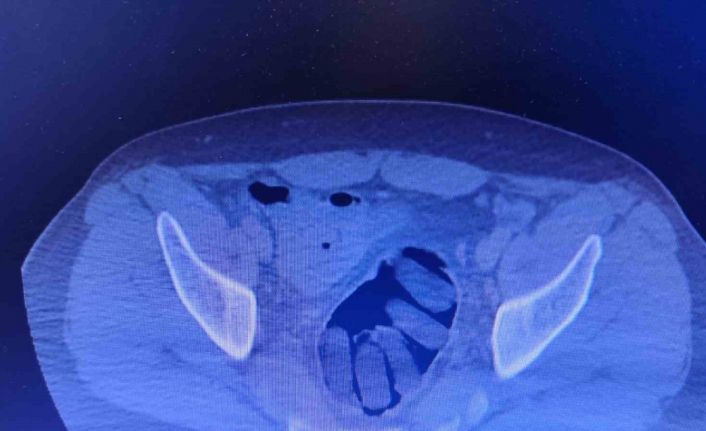

Kırşehir İl Emniyet Müdürlüğü Narkotik Suçlarla Mücadele Şube Müdürlüğü ekipleri tarafından yapılan çalışmalarda yabancı uyruklu Y.S. ve H.S.’nin doğu illerinden ülkeye kaçak yollarla girdikleri ve batı illerine uyuşturucu madde kuryeliği yaptıkları tespit edildi. Takibe alınan uyuşturucu kuryelerinin seyahat ettiği yolcu otobüsü Kırşehir’de durduruldu. Gözaltına alınan ve hastaneye götürülen şahısların midelerinde kapsül bulunduğu tespit edildi. Şahısların midelerinde zulaladığı 126 kapsül halinde 1 kilo 300 gram ve 44 kapsül halinde 550 gram uyuşturucu madde ele geçirildi.